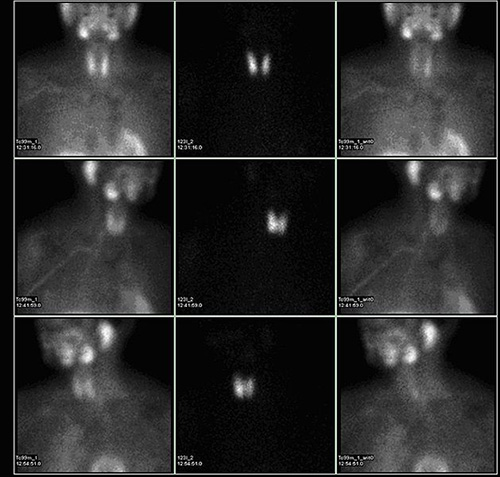

Mathieu Hatt, chercheur au Laboratoire de traitement de l’information médicale (Latim) à Brest vient de recevoir le « Bruce H. Hasegawa Young investigator medical imaging science award ». Ce prix récompense ses travaux au sein de l’équipe « imagerie multimodalité quantitative pour le diagnostic et la thérapie ». De son côté, la société SuperSonic Imagine vient de récolter 50 millions d’euros sur la plateforme Nyse Euronext afin de développer son échographie ultrasonore qui doit « révolutionne l’imagerie médicale »(4).

La recherche et l’innovation mobilisent des financements

L’institut Langevin qui constitue unité Inserm 979 vient par exemple de développer un appareil d’élastographie qui deviendra « outil incontournable ». De même, le Professeur Sigaux, Directeur de la Recherche et de l’Innovation à l’Institut national du cancer suit les travaux de l’Institut national de la santé et de la recherche médicale sur les dépistages précoces du cancer des poumons, et prépare un appel d’offre pour 2015(5). Après la publication obtenue dans la revue médicale anglo-saxonne, Plos One, le chercheur Paul Hoffman s’inquiète de la possibilité « que d’autres équipes s’emparent du projet, notamment en Amérique du Nord ».